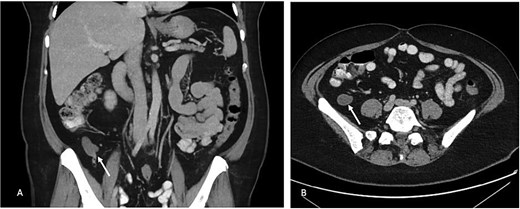

A 49-year-old woman was found to have an incidental 48 × 26 × 19 mm appendiceal mucocoele of the distal appendix on computer tomography (CT) scan of the abdomen and pelvis (Fig. 1). This was on a background of several month history of low grade right lower quadrant discomfort. The CT scan was conducted for assessment of unrelated left sided abdominal pain which was attributed to epiploic appendagitis. Her medical background included supraventricular tachycardia, partial thyroidectomy, hypertension, dyslipidaemia and previous hysterectomy for fibroids.

(A) Portal venous phase coronal slice of CT image with arrow pointing to dilated tip of the appendix. (B) Axial slice of same.